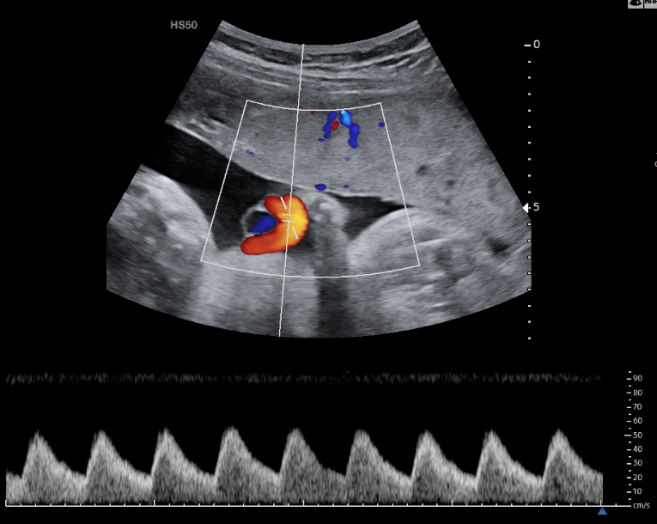

Εικόνα 01 και Εικόνα 02: Φυσιολογική καμπύλη Doppler δεξιάς και αριστερής Μητριαίας Αρτηρίας